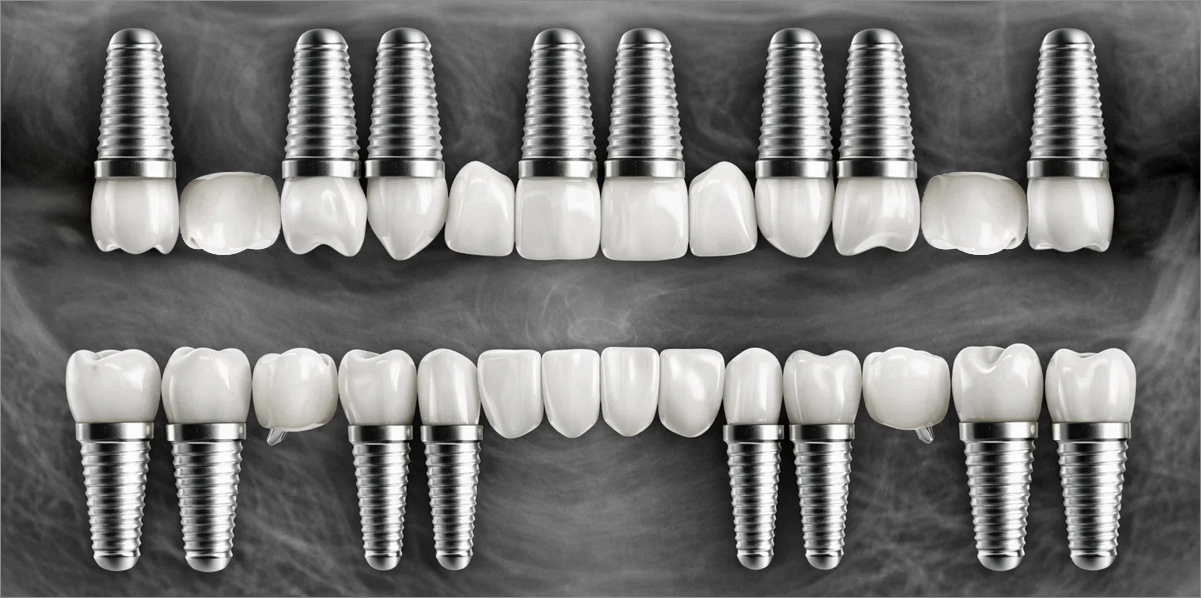

전체 임플란트는 위턱과 아래턱의 교합, 잇몸뼈의 상태 및

얼굴 변화 등 모든 것을 고려해 식립해야 합니다.

서울더자연치과는 3D 디지털 기술의 정밀 진단을 바탕으로

수술 계획을 세워 수술을 집도합니다.